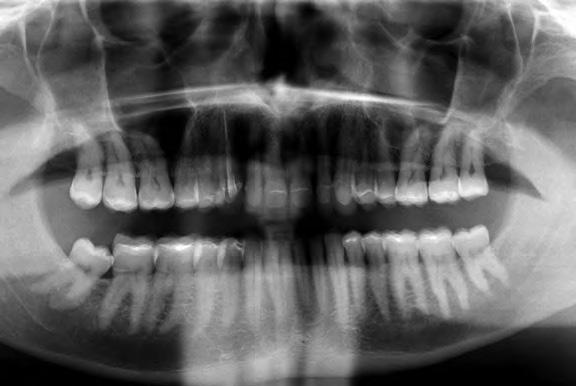

gyorsan és költség - Dr. Miguel Stanley, dr. Ana Gomes Paz, dr. Inês Miguel (Portugália) Dr. Christian Coachman (Brazília) 1. ábra: Kiindulási állapot (frontális irányból). 2. ábra: A kiindulási állapotról okkluzális irányból készített felvétel (felső állcsont). 3. ábra: A kiindulási állapotról okkluzális irányból készített felvétel (alsó állcsont). 4. ábra: A kiindulási állapotról készült panorámaröntgen felvétel (2015).

2015-ben egy 47 éves férfi páciens állkapocs-ízületi panaszai miatt kereste fel a rendelőnket. Ezen felül esztétikai problémát jelentett számára, hogy az egyik felső nagymetszőfogán lévő héj eltört (1-3. ábrák). A klinikai és radiológiai vizsgálatot követően megállapítható volt, hogy a páciens kifejezett bruxizmusa miatt csökkent a harapási magassága, és jelentős mennyiségű saját foganyagot abradált el (4. ábra)